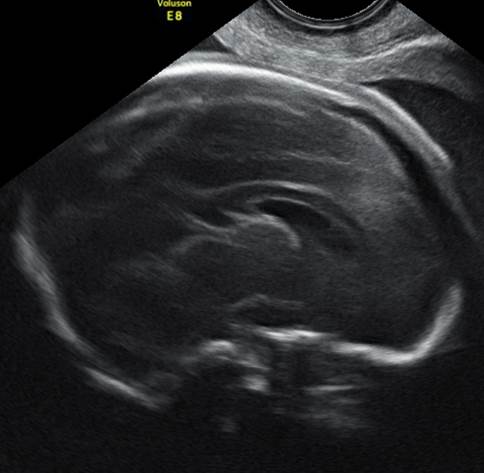

Вопрос 1

32 недели. Диагноз? Прогноз?